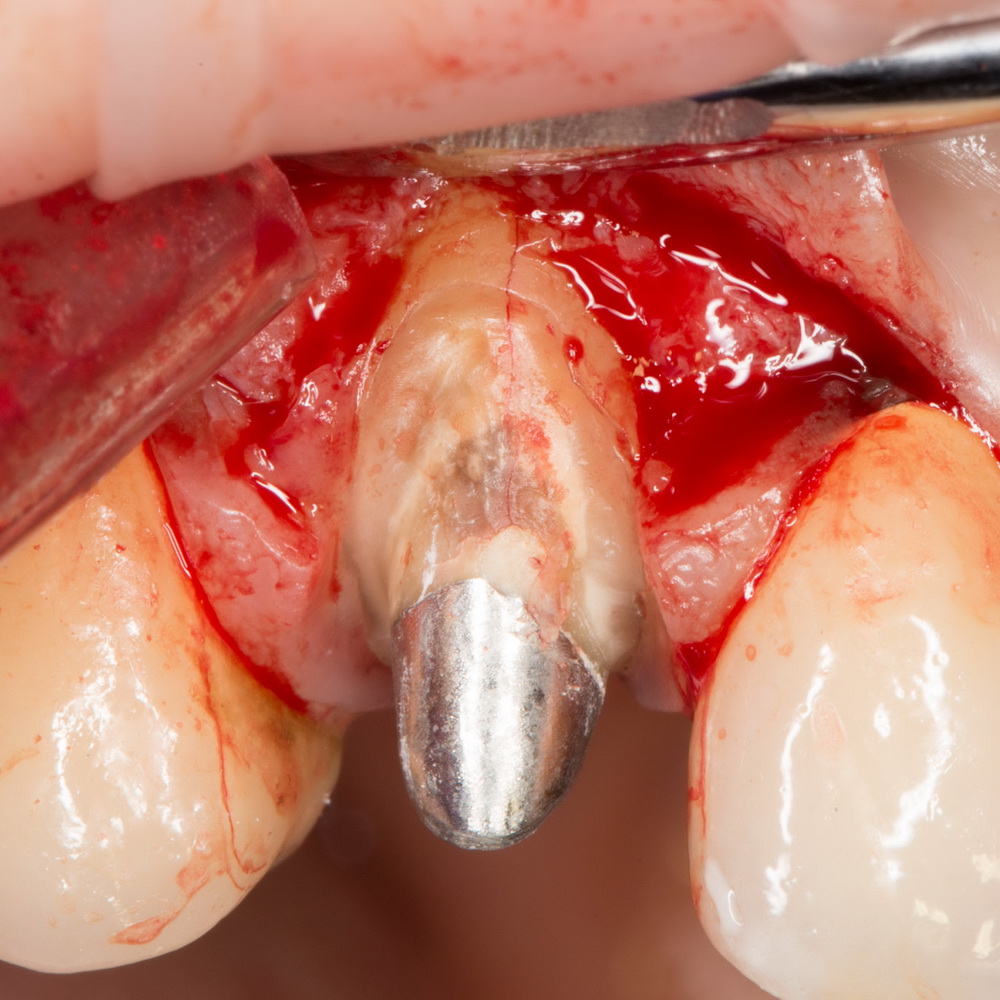

Это мой самый любимый и тщательно подготовленный проект — семинар по немедленной имплантации. Он уже дважды был в Москве, и однажды — в Нижнем Новгороде. На этот раз, мы проводим его совместно с компанией APEX в Санкт-Петербурге, и посвящен он будет… догадайтесь с трех раз?))) Через фокус немедленной имплантации будут рассмотрены различные имплантационные системы, операции остеопластики, синуслифтинга, удаления зубов и превентивной аугментации лунок.

Как видно из названия, семинар посвящен самой частой и распространенной хирургической операции в мире — удалению зубов. Это новое мероприятие в моем графике, мы проводим его совместно с IDA (International Dentistry Association). В ходе семинара будут рассмотрены различные методики удаления зубов, в том числе удаление ретинированных зубов мудрости, сверхкомплектных зубов, а также операции, включающие в себя эту процедуру: немедленная имплантация и превентивная аугментация лунок.